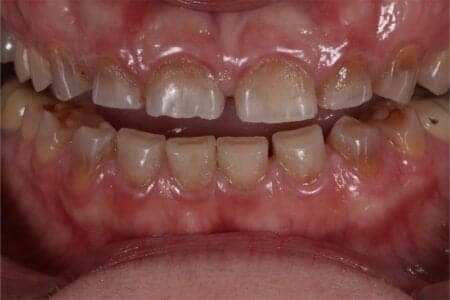

Mónica es un caso de desgastes muy severo y dientes con tinciones por haber tomado antibióticos con tetraciclina cuando era pequeña.

Se ha reestablecido el tamaño perdido de los dientes por los desgastes con incrustaciones y en la parte exterior del diente se han puesto carillas de porcelana.

Mónica es una paciente estupenda que aun teniendo mucho miedo era consciente de sus problemas de bruxismo (apretar los dientes) y desgastes. Además no le gustaba el color de sus dientes tan oscuros. De manera que reestablecimos la estética y la función masticatoria con incrustaciones de cerámica y carillas de porcelana.

Para evitar las fracturas y desgastes de nuevo, Mónica usa de manera continuada una férula de descarga.